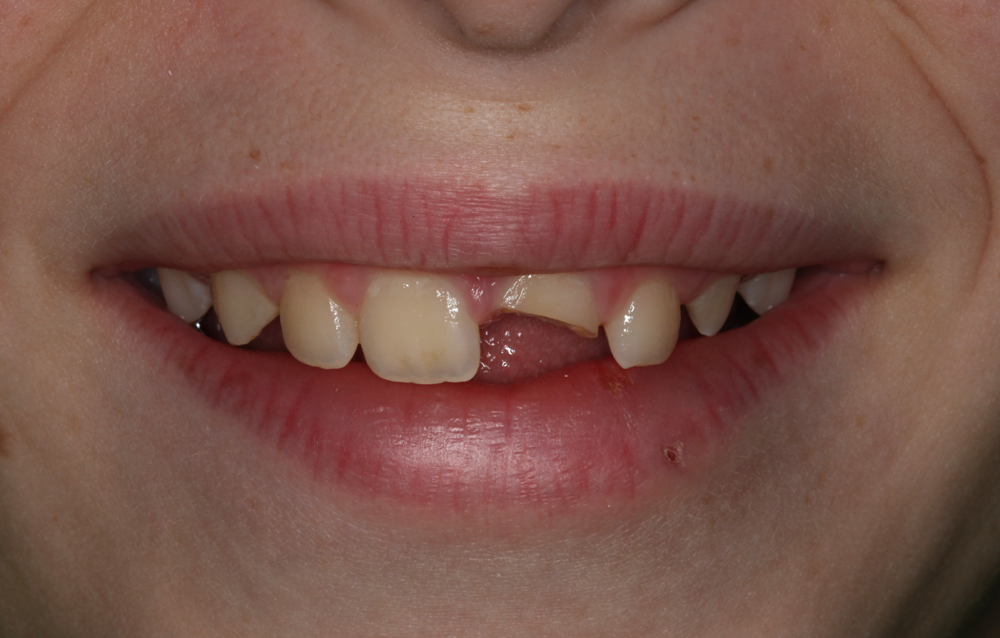

A 12-year-old male presented for a consultation for the restoration of the maxillary left central incisor (tooth No. 9), which was fractured when the patient was hit with a hockey stick while playing in gym class at school (Figs. 1 and 2). The patient had undergone endodontic treatment performed by an endodontist to stabilize the tooth one week earlier, and his parents were referred to the author via the American Academy of Cosmetic Dentistry (AACD) website.

Fig. 1 Fig. 2